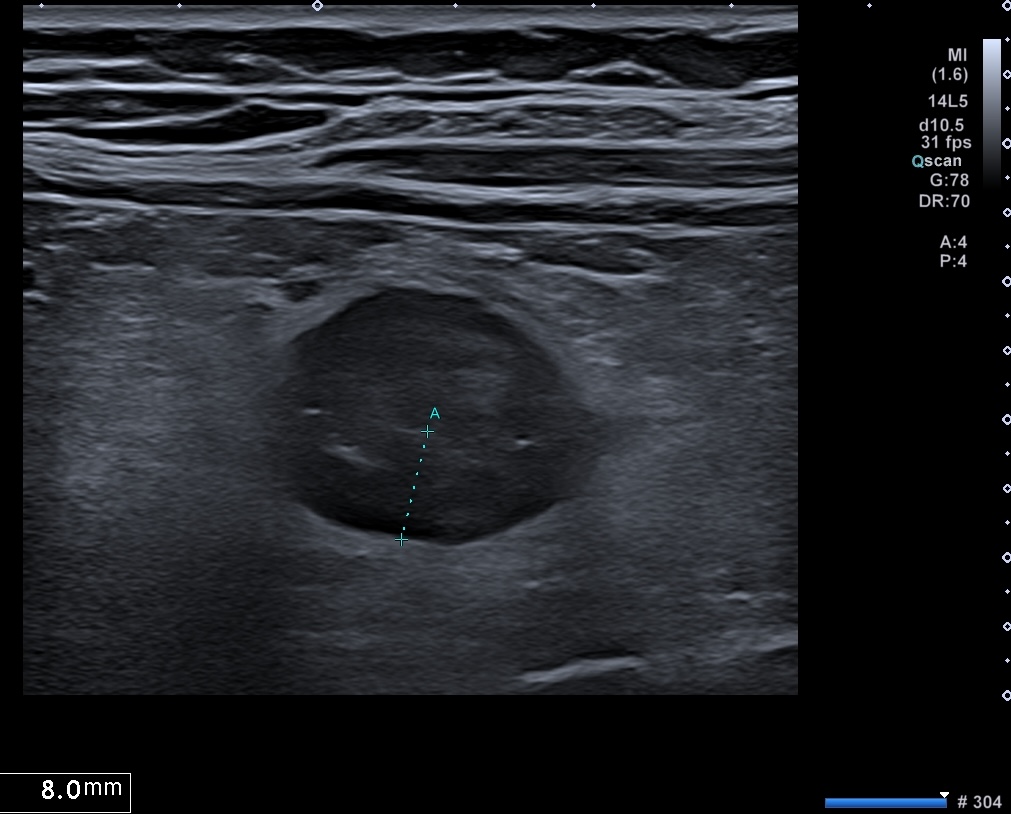

C'est la forme chronique de l'inflammation de la graisse, l'inflammation devient scléreuse, figée arrondie, plus hypoéchogène

- attraction de la séreuse en profondeur qui prend un aspect spiculé

- plus hypoéchogène

- Déformant la paroi localement

Sclérolipomatose antérieure iléon, graisse hypo échogène paroi Limberg 1 au maximum